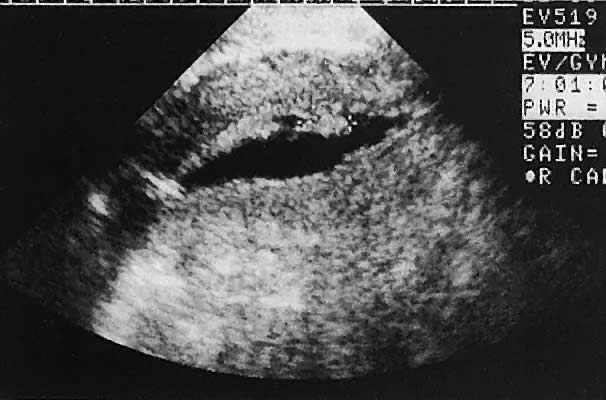

Intrauterine Devices

Ultrasonographic localization of intrauterine devices has been possible for years (Fig. 46). The advent of transvaginal scanning increases the accuracy of intrauterine device localization.127 Removing intrauterine devices under transabdominal ultrasound guidance offers a more precise and potentially less traumatic removal in difficult clinical settings.128,129 The ability to extract an intrauterine device that is juxtaposed, but inferior to, an early intrauterine pregnancy also is occasionally enhanced by transabdominal ultrasound guidance.

Fig. 46. Transabdominal scan depicts Lippes loop in situ, cervix (CX), fundus, bladder, and vagina.